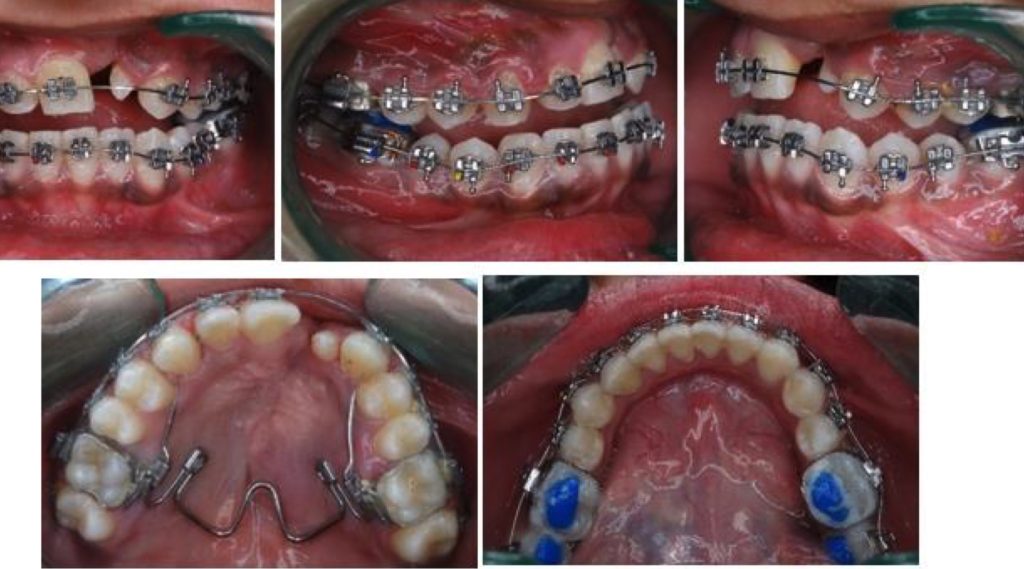

El artículo que compartimos hoy se trata sobre el tratamiento ortodóntico de un paciente con fisura labiopalatina unilateral, específicamente utilizando un expansor palatino de NiTi. El informe de caso describe cómo se abordaron las dificultades relacionadas con la maloclusión, la discrepancia maxilofacial y las complicaciones causadas por el labio y paladar fisurados, mediante una expansión maxilar suave y otros procedimientos ortodónticos, con el objetivo de mejorar la estética, la función y la estructura facial del paciente sin recurrir a cirugía ortognática.

También destaca la importancia de un enfoque interdisciplinario en el manejo de pacientes con fisura labiopalatina. El artículo se llama Arch expansion using niti palatal expander in cleft lip and palate patient: A case report y ha sido publicado en el Journal of Contemporary Orthodontics.